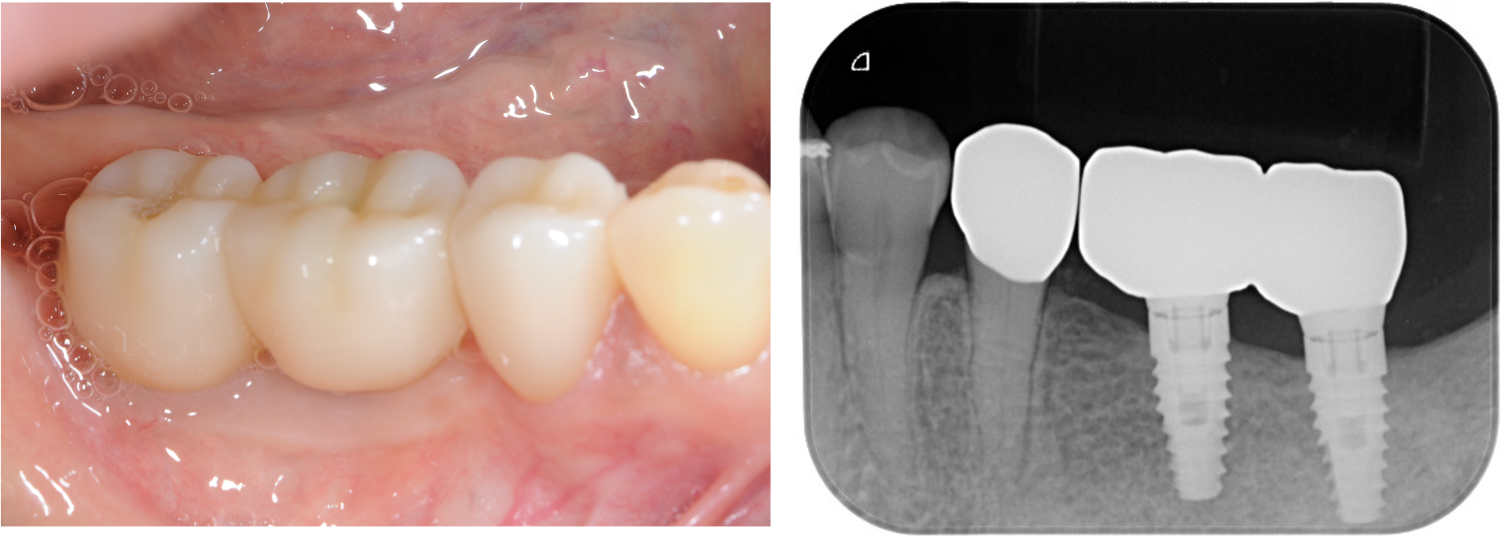

| 主訴 | 全顎治療希望、右下の歯が動いて痛いので噛みずらい。当院でインプラント治療したお母様からの紹介 |

| 治療内容 | プラークコントロール不良なため歯周治療を行い、保存不能の歯を抜歯し、抜歯窩の治癒を待って、欠損部にインプラントを施し咬合再構成を行う。 プロビジョナルレストレーションによる咬合関係を模索した後、全顎にわたりセラミックによる補綴治療、その後メインテナンスに移行 |

| 治療費 | 3,020,000円(税込)(インプラントすべて含む) |

| 治療期間 | 8ヶ月 |

| 治療回数 | 48回 |

| 想定されたリスク | 食いしばり(パラファンクション)によるセラミックの破折、歯の破折 |